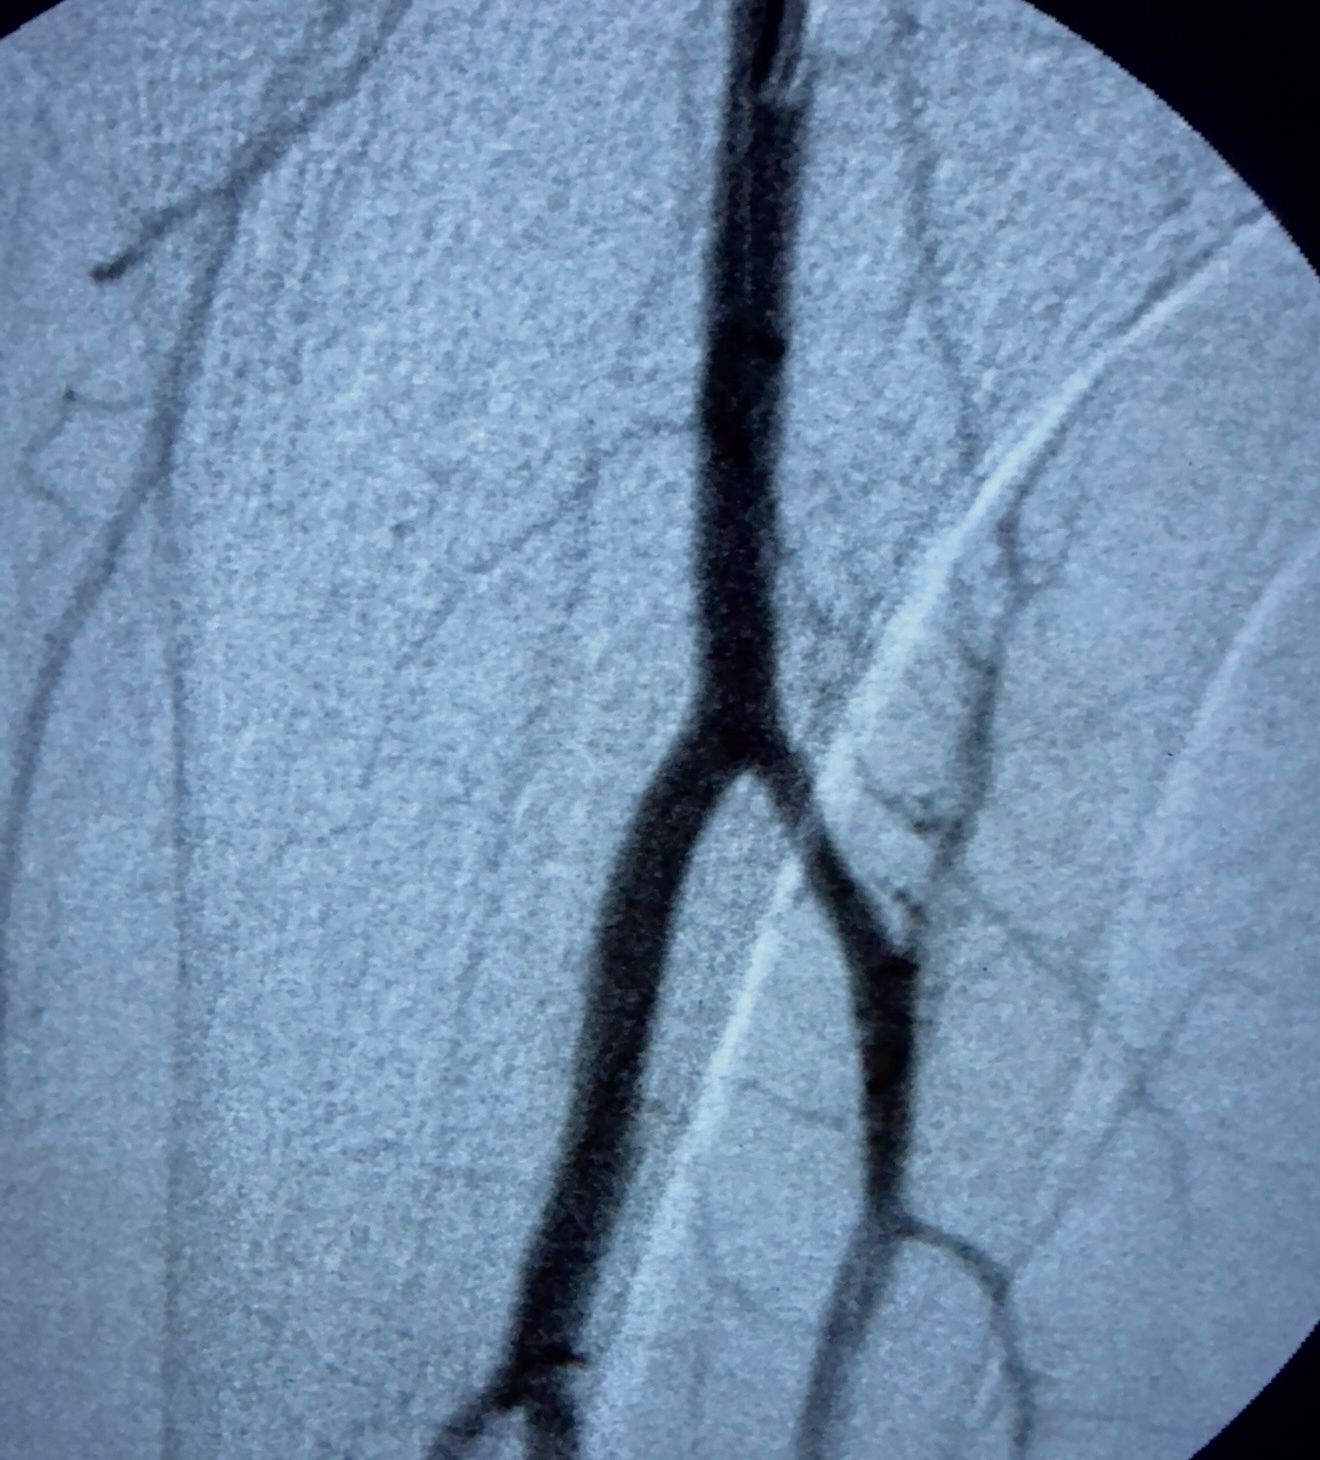

“A patient with acute thrombosis involving the anterior tibial artery and the tibioperoneal trunk was referred to me for management. In our country, we have no access to dedicated mechanical thrombectomy devices or catheter-directed thrombolysis.

Faced with this challenge, I improvised a solution:

- Took a 5 Fr multipurpose catheter and cut its tip with a scalpel at the wider portion.

- Connected it to a 50 cc syringe to generate strong negative suction.

- Performed targeted aspiration of the thrombus within the anterior tibial artery and the tibioperoneal trunk.

Outcome: Complete removal of clots, with final angiography confirming full recanalization and no distal embolization.

This case illustrates how, even in resource-limited settings, with creativity, technical skill, and determination, effective endovascular solutions can be achieved to preserve limb viability.”